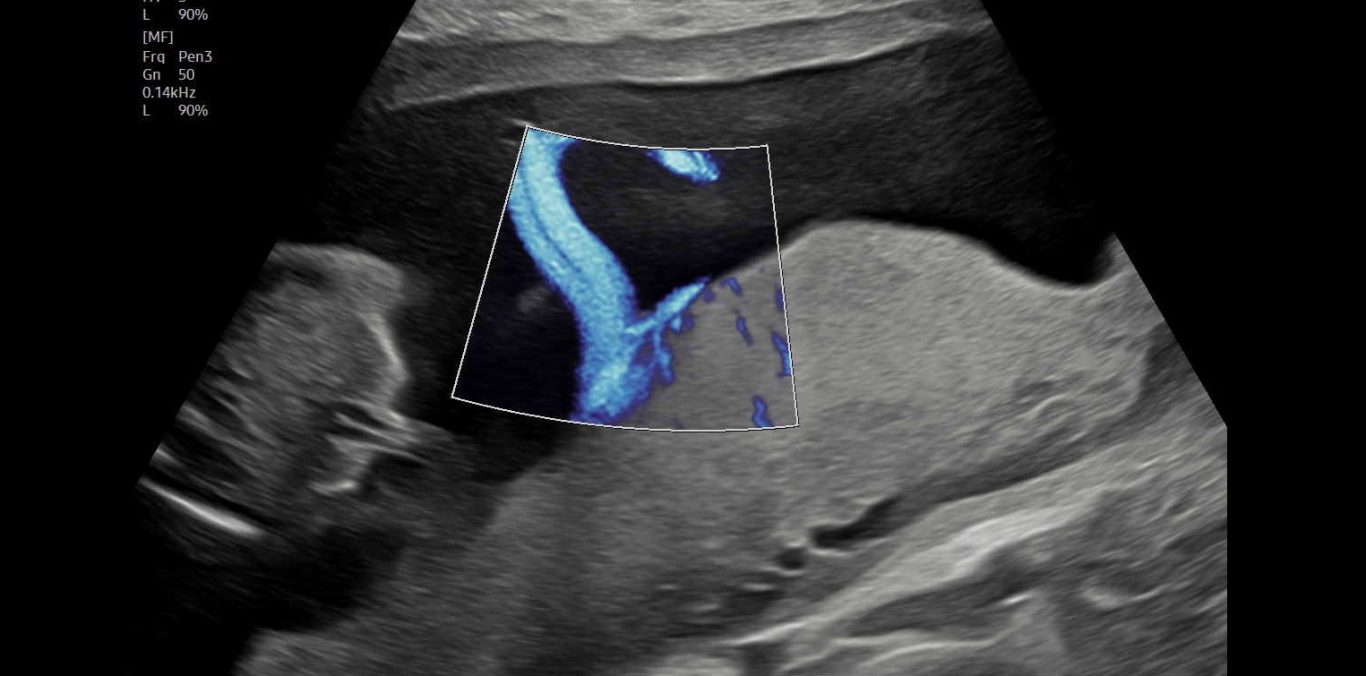

Doppler

Bei dieser Untersuchung messen wir die Durchblutung in der Nabelschnur und anderen Blutgefäßen, um die Versorgung Ihres Kindes zuverlässig einzuschätzen und zu überwachen. Je nach Fragestellung ist diese Untersuchung ab 11 SSW möglich.